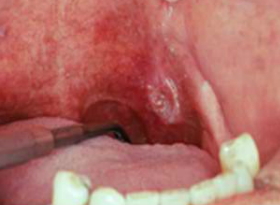

Dấu hiệu sớm của ung thư miệng

Những dấu hiệu sớm của ung thư miệng là gì? Ung thư miệng là do sự tăng trưởng và sinh sản không kiểm soát của các tế bào ở một số vùng của miệng. Nó có